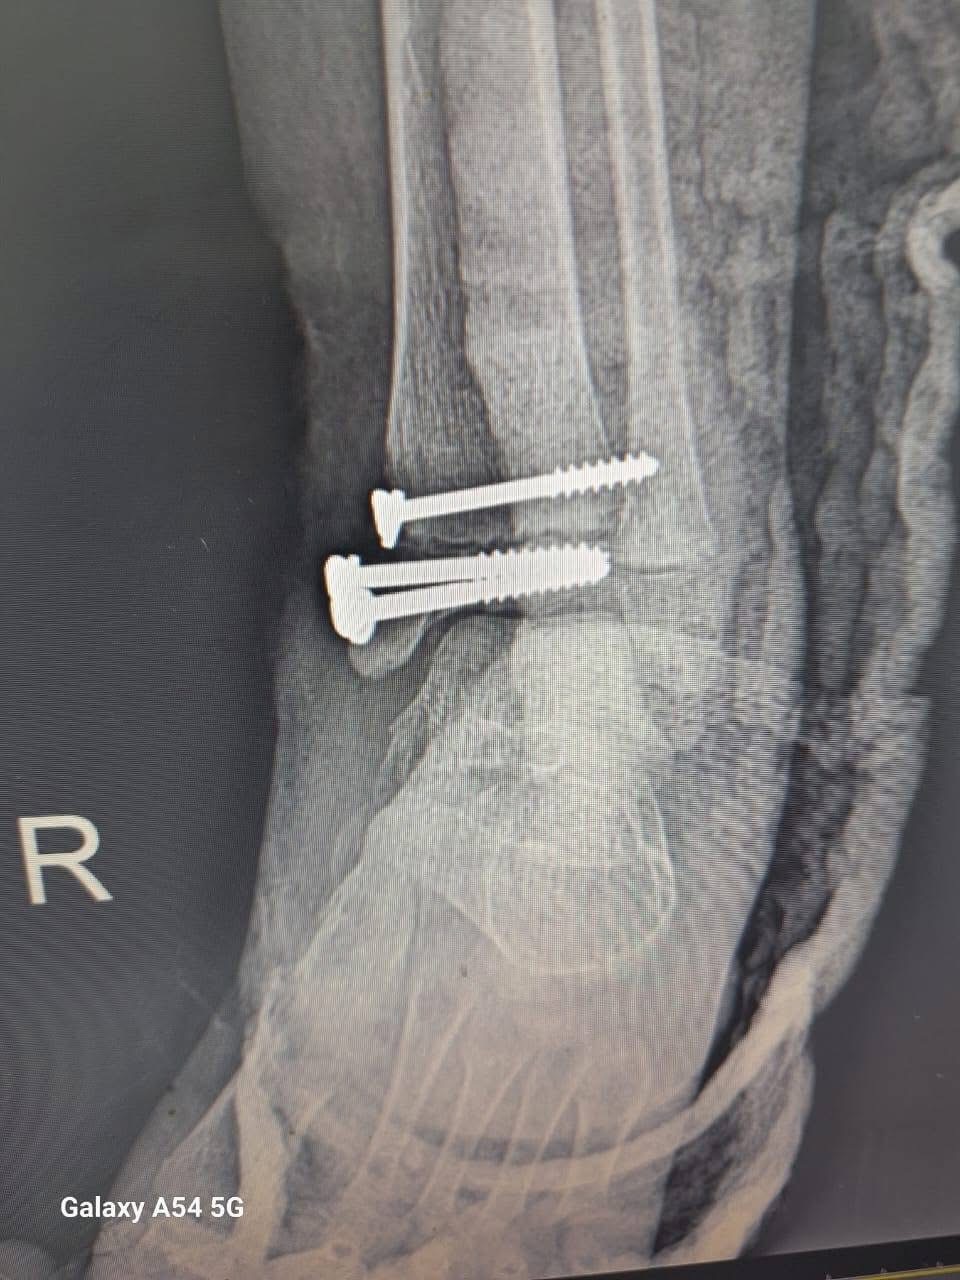

وأضاف الخضيري، أنه تم إجراء 3 عمليات بقسم الأنف والأذن، و3 عمليات بقسم العظام، بالإضافة إلى 4 عمليات جراحية متنوعة، بما يعكس جاهزية الأقسام المختلفة بالمستشفى لتقديم خدمات طبية متكاملة للمرضى